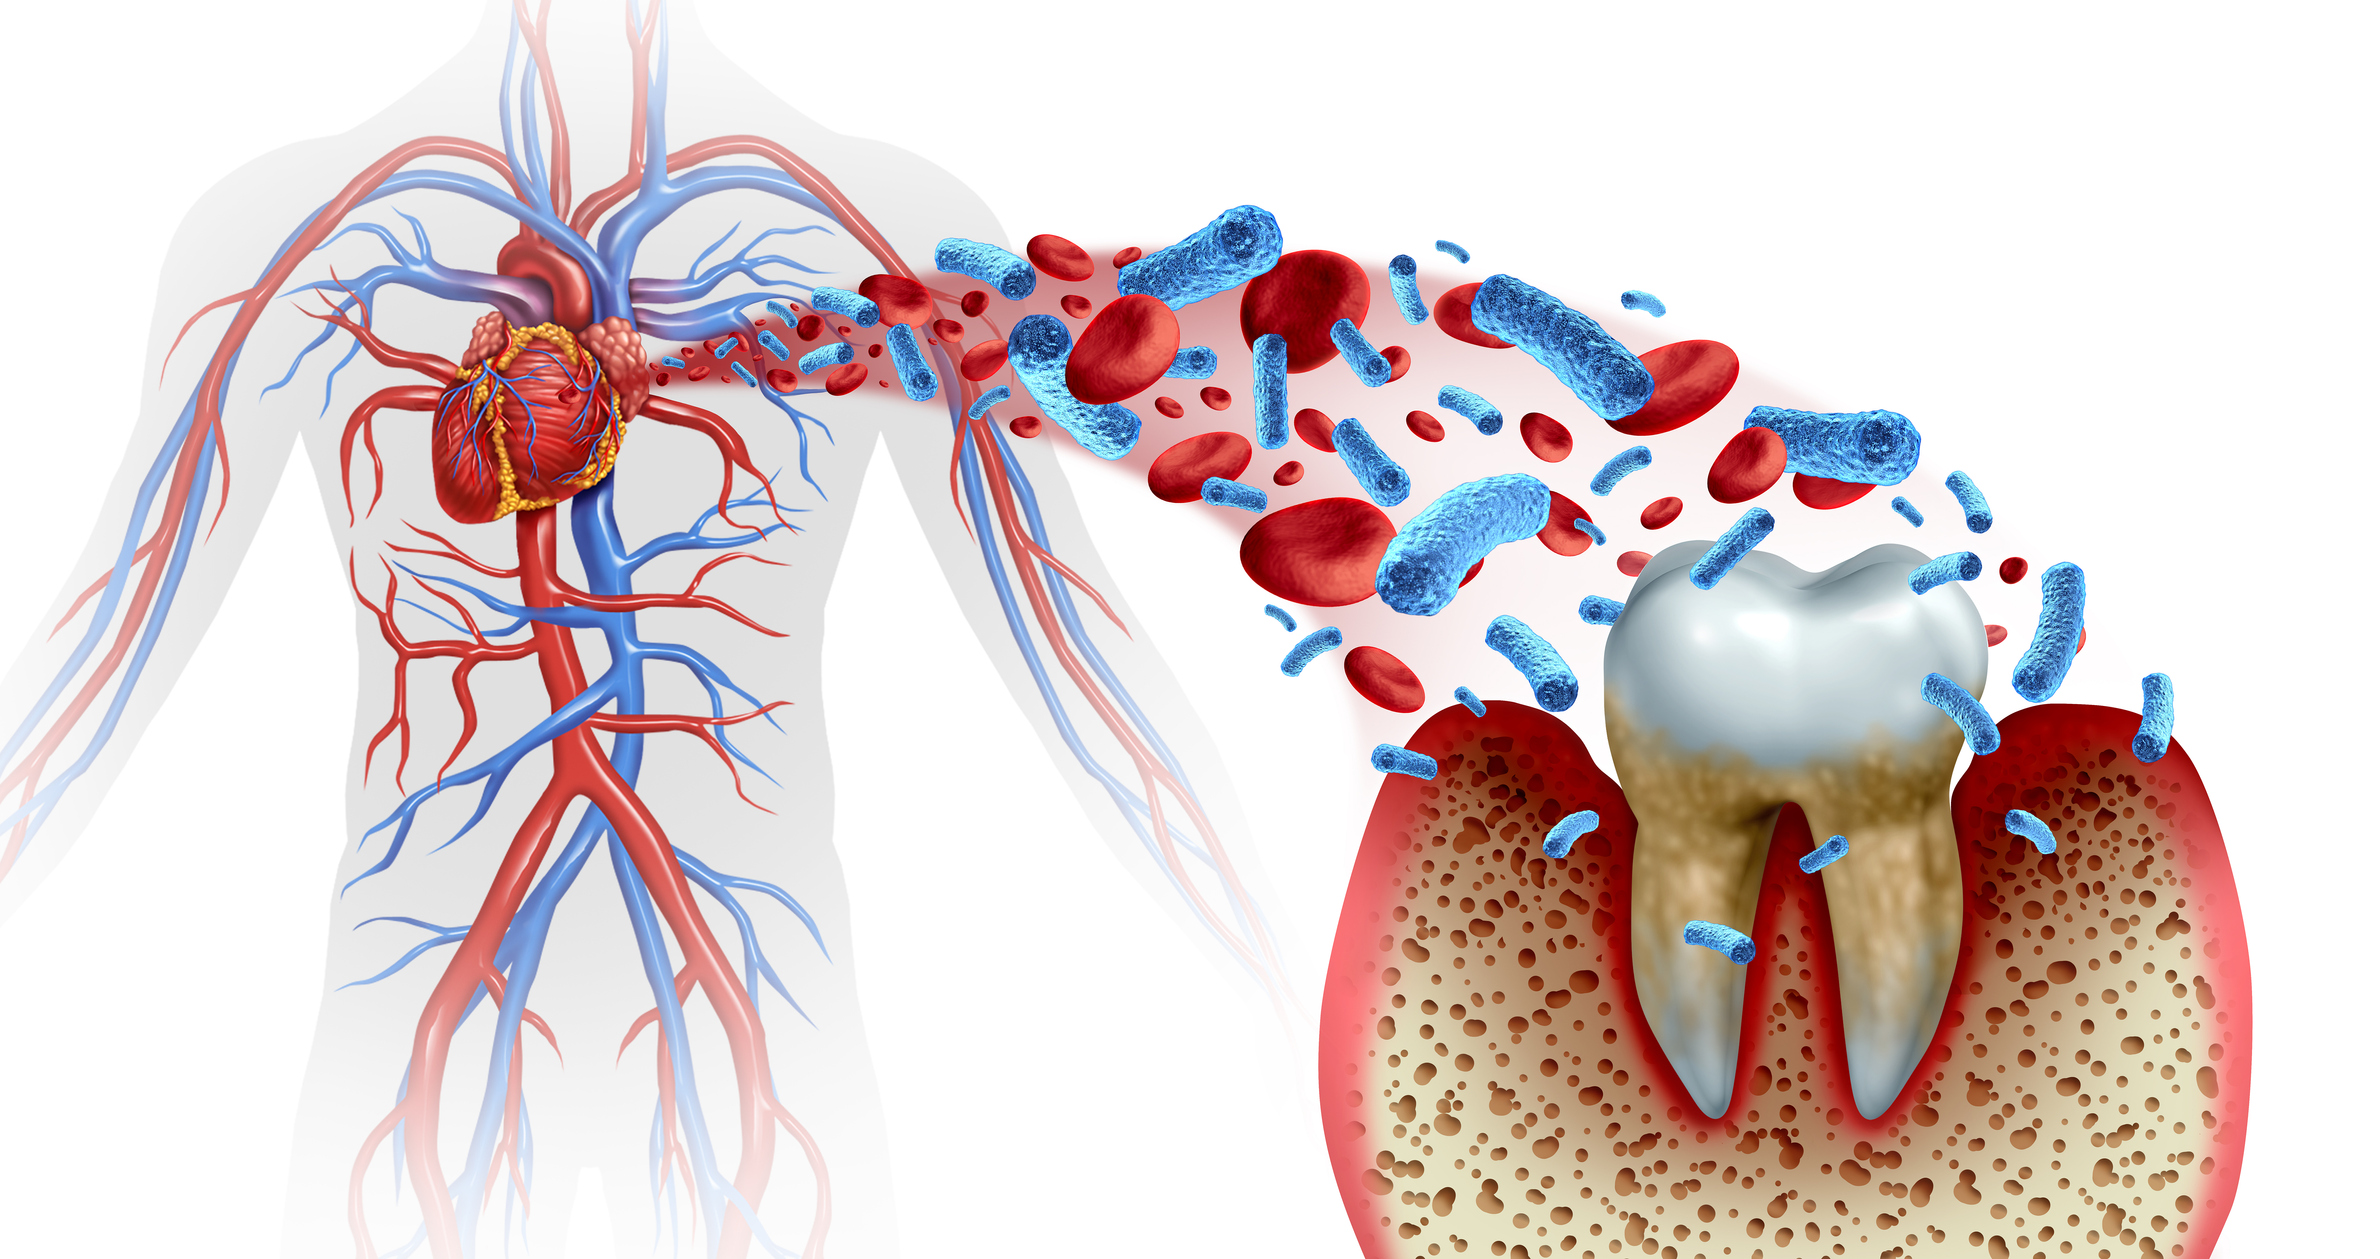

- Allgemeinerkrankungen Eine schlechte Mundhygiene hat nachweislich einen negativen Ein-fluss auf diverse allgemeine Erkrankungen. Umgekehrt dient eine gute Mundpflege der Infektionsprophylaxe und kann sogar kognitive und motorische Beeinträchtigungen verringern. Gerade im Alter ist es wichtig, einen möglicherweise bereits kompro-mittierten Allgemeinzustand stabil zu halten und Klinikeinweisungen zu vermeiden. In diesem Zusammenhang spielt das Erkennen von Risikogruppen und Risikofaktoren eine große Rolle, auch mit Hinblick auf das im Expertenstandard vorgeschlagene Verfahren des Screenings und Assessments.

- Allgemeinerkrankungen Eine schlechte Mundhygiene hat nachweislich einen negativen Einfluss auf diverse allgemeine Erkrankungen. Umgekehrt dient eine gute Mundpflege der Infektionsprophylaxe und kann sogar kognitive und motorische Beeinträchtigungen verringern. Gerade im Alter ist es wichtig, einen möglicherweise bereits kompromittierten Allgemeinzustand stabil zu halten und Klinikeinweisungen zu vermeiden. In diesem Zusammenhang spielt das Erkennen von Risikogruppen und Risikofaktoren eine große Rolle, auch mit Hinblick auf das im Expertenstandard vorgeschlagene Verfahren des Screenings und Assessments.